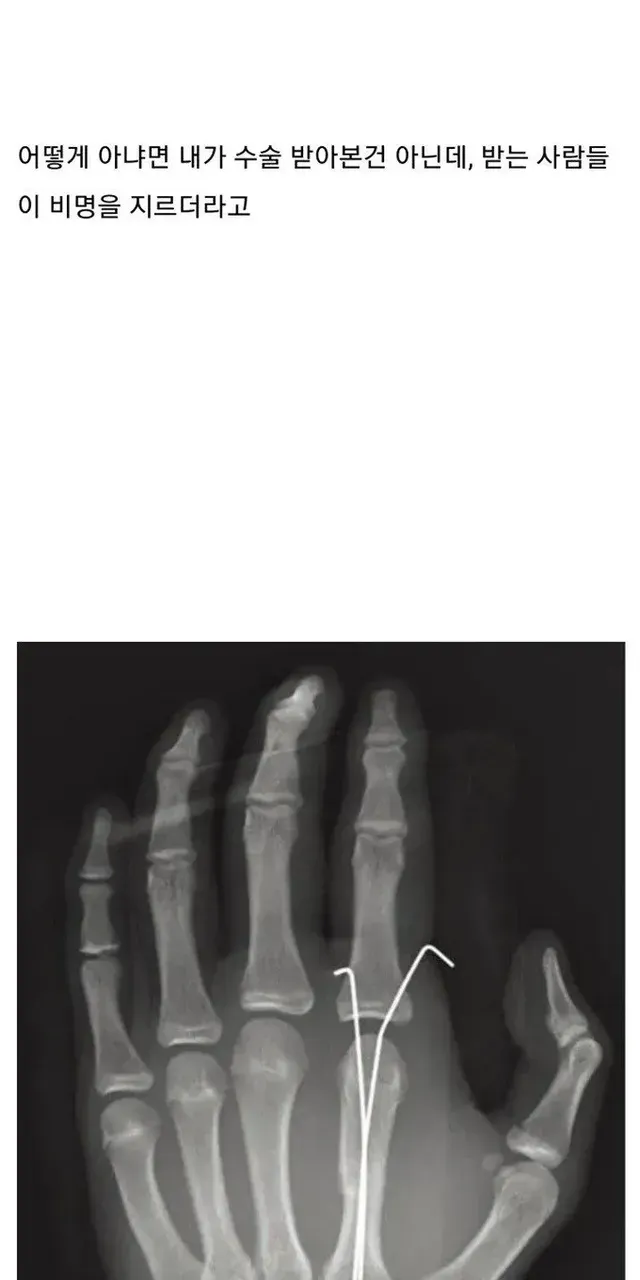

[스압] 뼈 안 부러져본 사람들이 의외로 모르는 사실,,